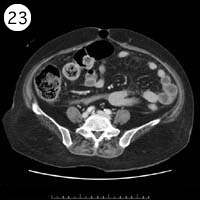

57歳 女性

単純CT

造影CT

※異常画像を赤枠で示しています